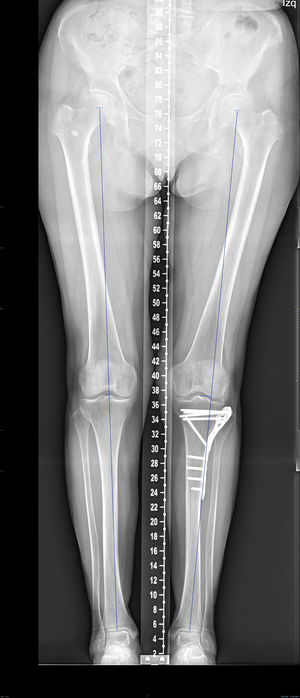

En la telemetría se analizó la desviación en mm del eje de carga respecto al miembro contralateral, el medial proximal tibial angle [MPTA) de ambos miembros y la diferencia en grados entre ellos (fig. 2).

En el análisis de la telerradiografía la diferencia de la desviación media del eje con respecto a la pierna contralateral fue de 12mm. La diferencia media del MPTA fue de −1,1grados.

El escalón medio medido en TC fue de 3,6mm (DE: 1,9mm). El área media medida en TC fue de 17,57cm2 (DE: 6,1cm2) El slope medio fue 12,3grados (DE: 5,3grados).